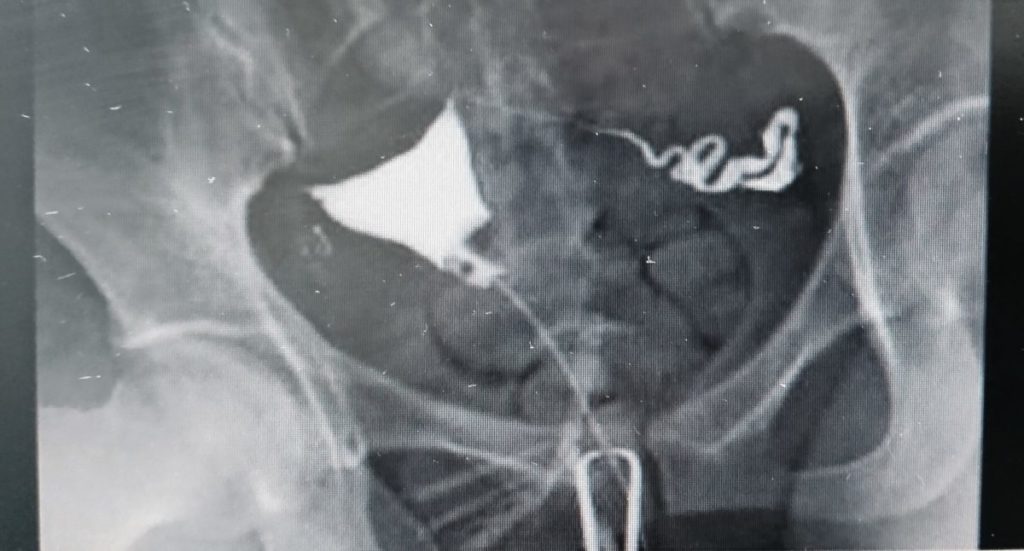

この検査は、子宮の入り口から子宮、卵管へ造影剤を流すことにより、卵管が通っているか、どの辺りが詰まっているのか、通り方に異常はないのか、卵管周辺に異常がないかを調べることが出来ます。また子宮の形や子宮内膜の異常、子宮内膜ポリープがあるのも確認することができます。

この卵管造影検査を受けられた方は、しっかり両側卵管が通っているのが確認できます。下腹部に我慢できる痛みがありましたが、検査終了後は特に痛みの訴えはありませんでした。